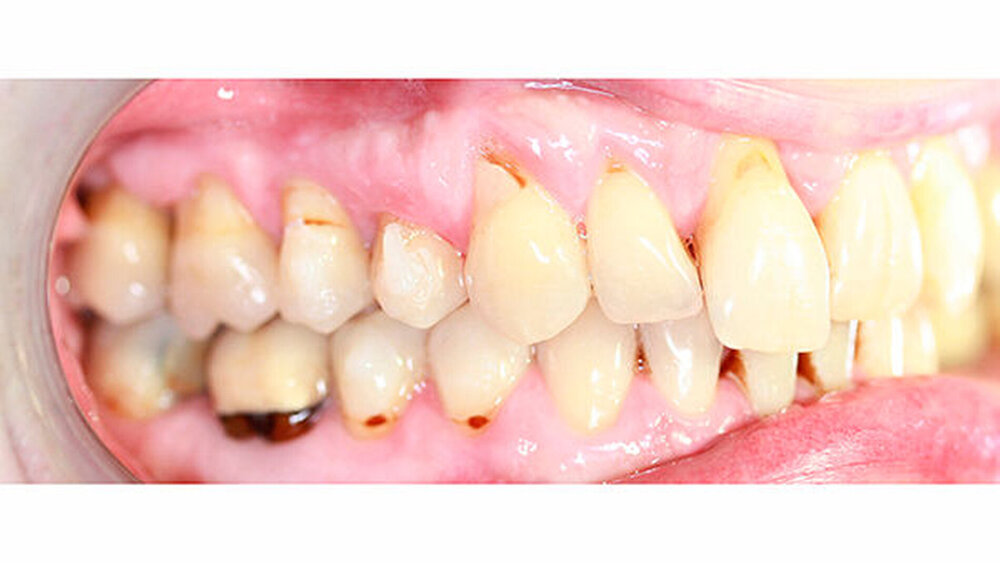

Kieferorthopädisch imponierte beidseits eine neutrale Verzahnung bei einem tiefen Biss von 5 mm - bedingt durch die Verlängerung beider Frontzahngruppen. Besonders Zahn 11 zeigte eine erhebliche Verlängerung und Protrusion mit einer sagittalen Frontzahnstufe von 5 mm. Sowohl die Frontzähne im Ober- als auch im Unterkiefer wiesen eine lückige Beziehung zueinander auf (Abbildung 1).

Röntgenologisch stellte sich im Orthopantomogramm der bereits intraoral ersichtliche horizontale und vertikale Knochenabbau mit Attachmentverlust an einzelnen Zähnen dar. Die Erhaltungswürdigkeit einzelner Zähne war aufgrund des starken Knochenverlustes beziehungsweise der Beeinträchtigung des Halteapparates als kritisch zu beurteilen.

Zudem wurde die Diagnose einer Parodontitis gestellt, die eine Rücküberweisung an den Hauszahnarzt erforderlich machte (Abbildung 2).